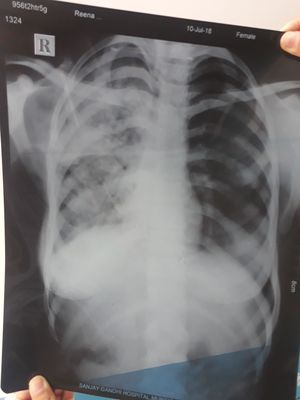

Ur comments pls!!!

20 yr old girl c/o cough fever breathlessness since 2 months.

Dr. Sunil

Pneumonia??